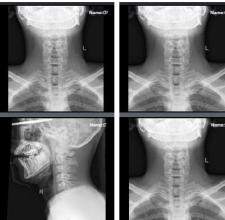

Background: Lawlessness is common among all walks of life: youth, adolescents, and adults. Incidents such as fights between students, murders, and misuse of traditional weapons are common and can lead to injuries or even death. The involvement of ‘sumpit’(blowgun), one of Indonesia's traditional weapons that are often used for violent purposes, often causes injuries that are very similar to those caused by modern weapons. This makes it difficult for medical and forensic experts to identify and analyze the cause of these injuries. In this study, we present the cases of three riot victims injured by chopstick throwing, examining the different injury patterns, the challenges faced by forensic teams, and the implications for health care providers and law enforcement. Case description: This case series describes three male patients(ages14,16,and19)who presented to the emergency department following a civil riot. All victims sustained penetrating trauma from projectiles launched from a traditional Indonesian sumpit. Clinical and forensic analyses revealed small, deep entry wounds mimicking low-velocity gunshot injuries, complicating initial assessment. Conclusion: Traditional weapons such as sumpit continue to pose a major challenge to medical experts and forensic professionals because the wounds inflicted have two separate but often co-occurring mechanisms: penetrative action and the risk of toxic poisoning. The results of this study highlight the urgent need for greater responsibility on the part of clinical and forensic practitioners, as well as increased public awareness. This study highlights the need for knowledge, preparedness, and ongoing medico legal care for trauma caused by conventional weapons by recording and examining these cases.